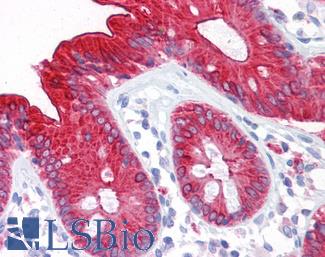

Villin

Anti-Villin antibody IHC of human small intestine, epithelial membrane. Immunohistochemistry of formalin-fixed, paraffin-embedded tissue after heat-induced antigen retrieval. Antibody LS-B8547 dilution 10 ug/ml.

MOC-31 (EPCAM)

Anti-EPCAM antibody IHC of human intestine. Immunohistochemistry of formalin-fixed, paraffin-embedded tissue after heat-induced antigen retrieval. Antibody LS-B5565 dilution 1:100.